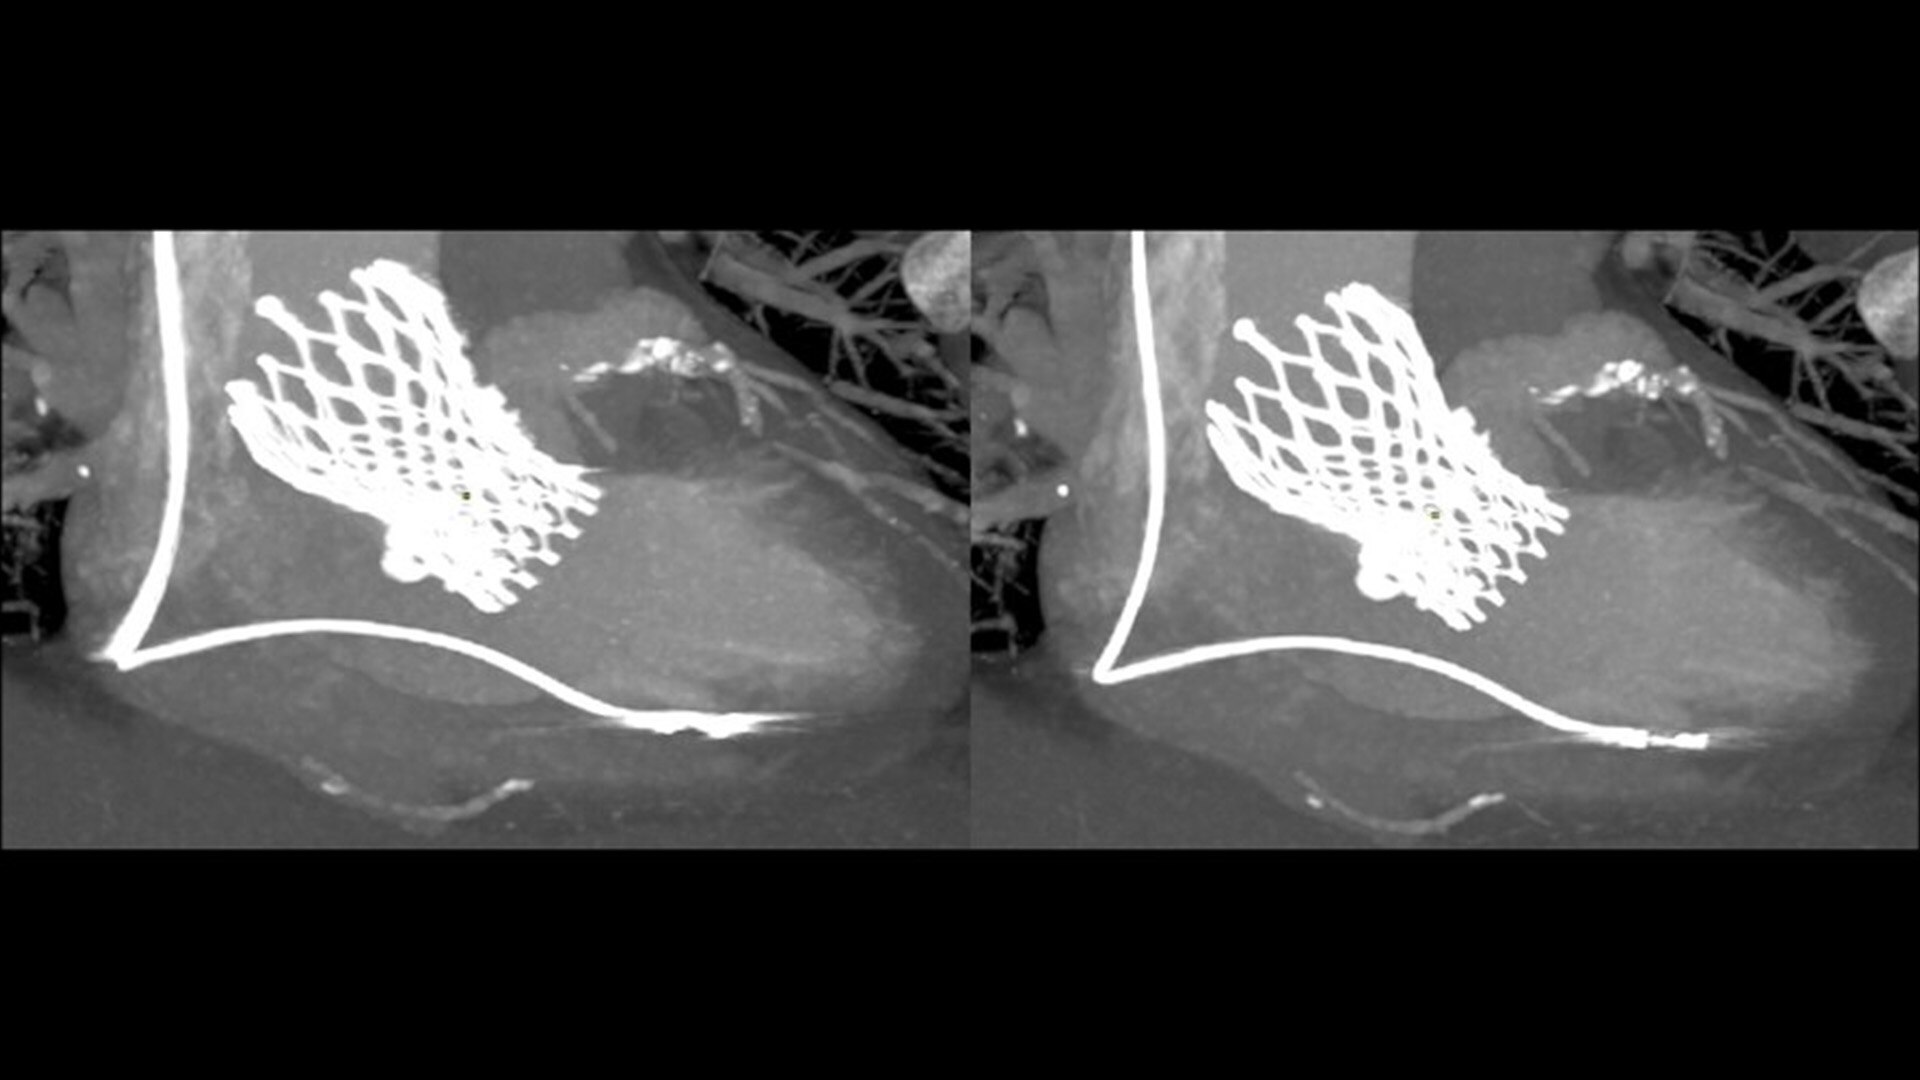

SnapShot Freeze 2

Intelligent and automated whole-heart motion correction for enhanced Cardiac CT imaging.

6x reduction in motion artifacts1

1. As demonstrated in mechanical and mathematical cardiac phantom testing